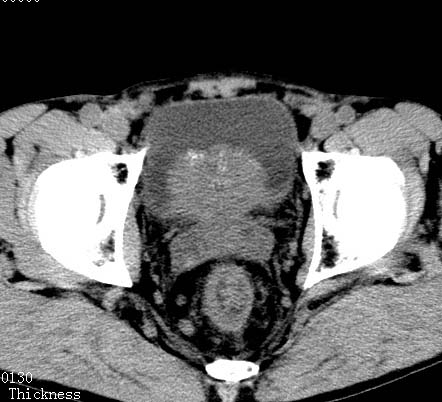

标题: CT17540:男 56岁 . [打印本页]

病人男 56岁 .

前列腺增生,膀胱后壁未见异常,精囊腺及精囊三角未见异常

前列腺增生 钙化!

支持 前列腺增生、钙化。

建议进一步检查除外前列腺癌.

考虑慢性前列腺,精囊炎;不除外前列腺癌

前列腺增生并钙化,可疑直肠占位

前列腺癌.